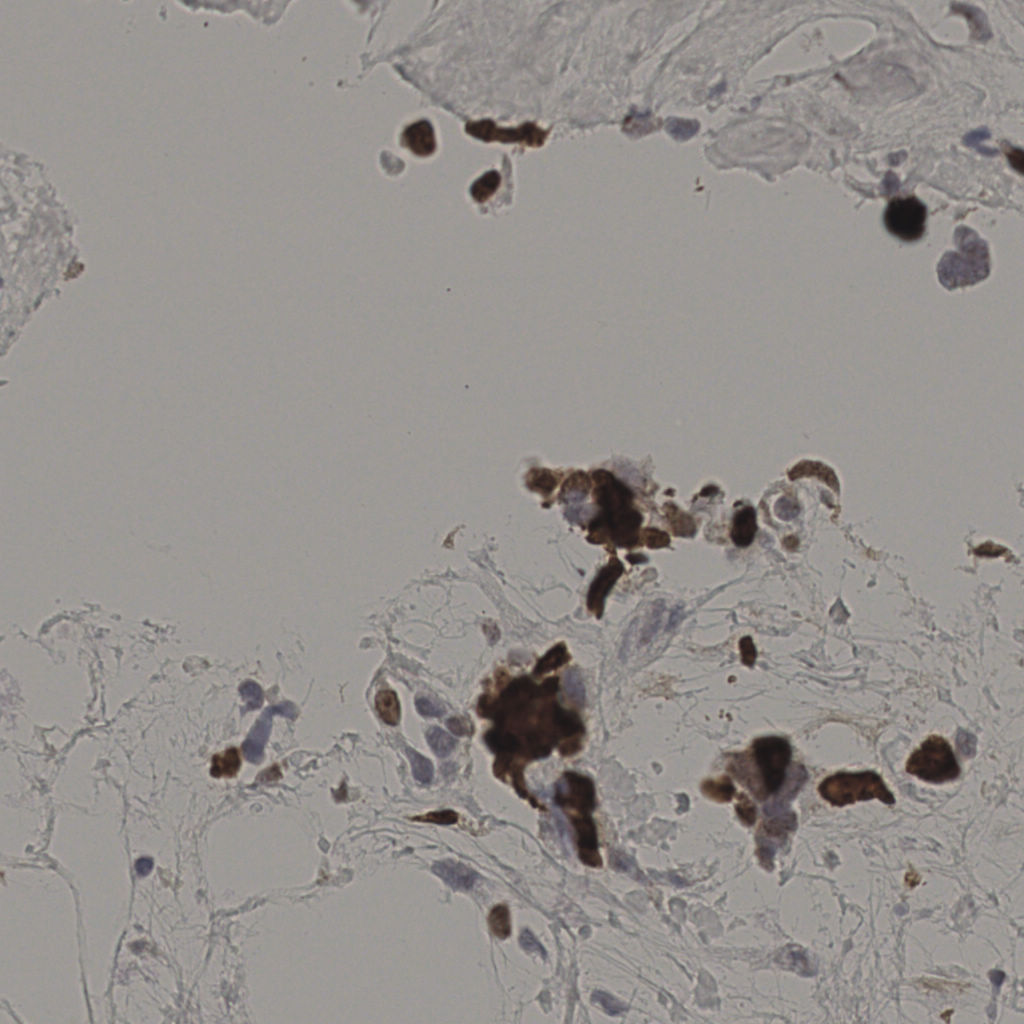

slice_28_25_x25088_y22400.png

slice_28_25_x2508...